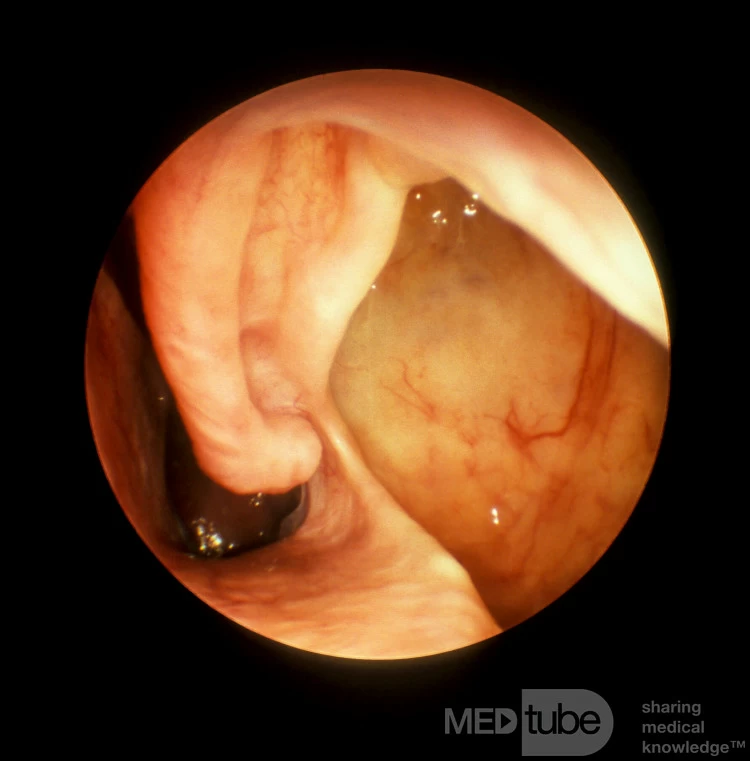

Lỗ thông dưới lớn

Bệnh nhân này có một lỗ thông mũi dưới rất lớn, qua đó có thể nhìn thấy rõ niêm mạc xoang hàm trên.